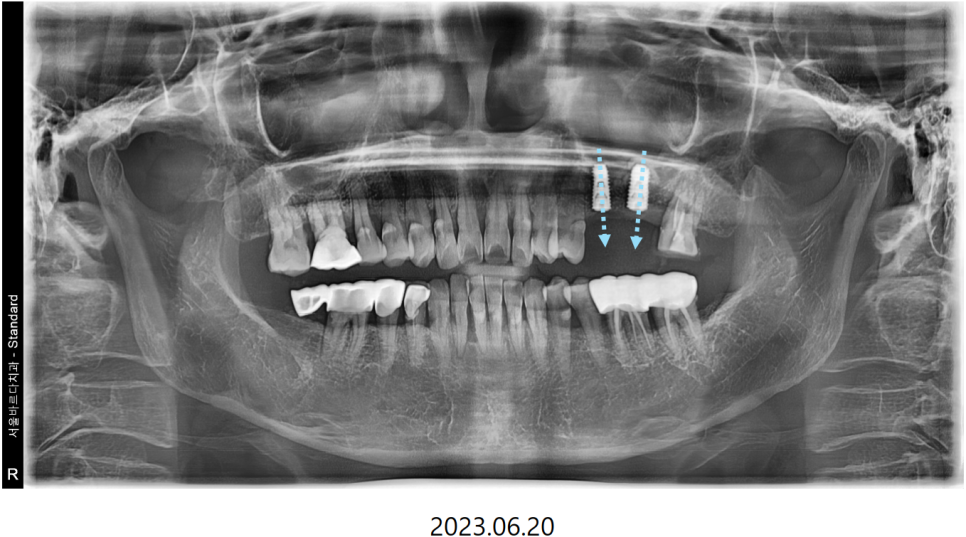

뿌리 끝 염증이 생겨 많이 흔들리는

첫번째 큰어금니와 그 앞의 작은 어금니를 발치 한 후

"상악동 거상술"과 함께 임플란트를 식립하기로 했습니다.

수술하기전에 삼차원 CT와 삼차원 구강 스캔 데이터를 가지고,

먼저 식립 위치를 시뮬레이션 해본 후

정확히 식립할 수 있는 네비게이션 장치를 제작합니다.

이를 맞춤장치를 제작한다고해서 "네비게이션 임플란트"라고 하는데요.

저희는 해당 디지털 기술을 적극 도입하여 뼈 상태가 좋은 자리에

정확하게 안전하게 시술하고 있습니다.

CT를 분석하여 미리 계획해둔 자리에

가이드를 장착하고 심은 덕분에

해당자리 상악동 손상없이 안전하게

상악동 거상술과 임플란트 식립을 마쳤습니다.

이번에 진행한 상악동 거상술은

상악동 수직 거상술로 수압을 이용해 막을 들어올려서

안쪽에 뼈를 채우고 해당자리에

계획한 굵기와 길이의 픽스처를 심을 수 있게 하는 방법입니다.

당일 시술은 모두 잘 마쳤고

이제 뿌리가 뼈에 잘 붙을 때까지

3-4개월 정도 충분히 기다린 후에

2차 수술을 진행할 예정입니다.